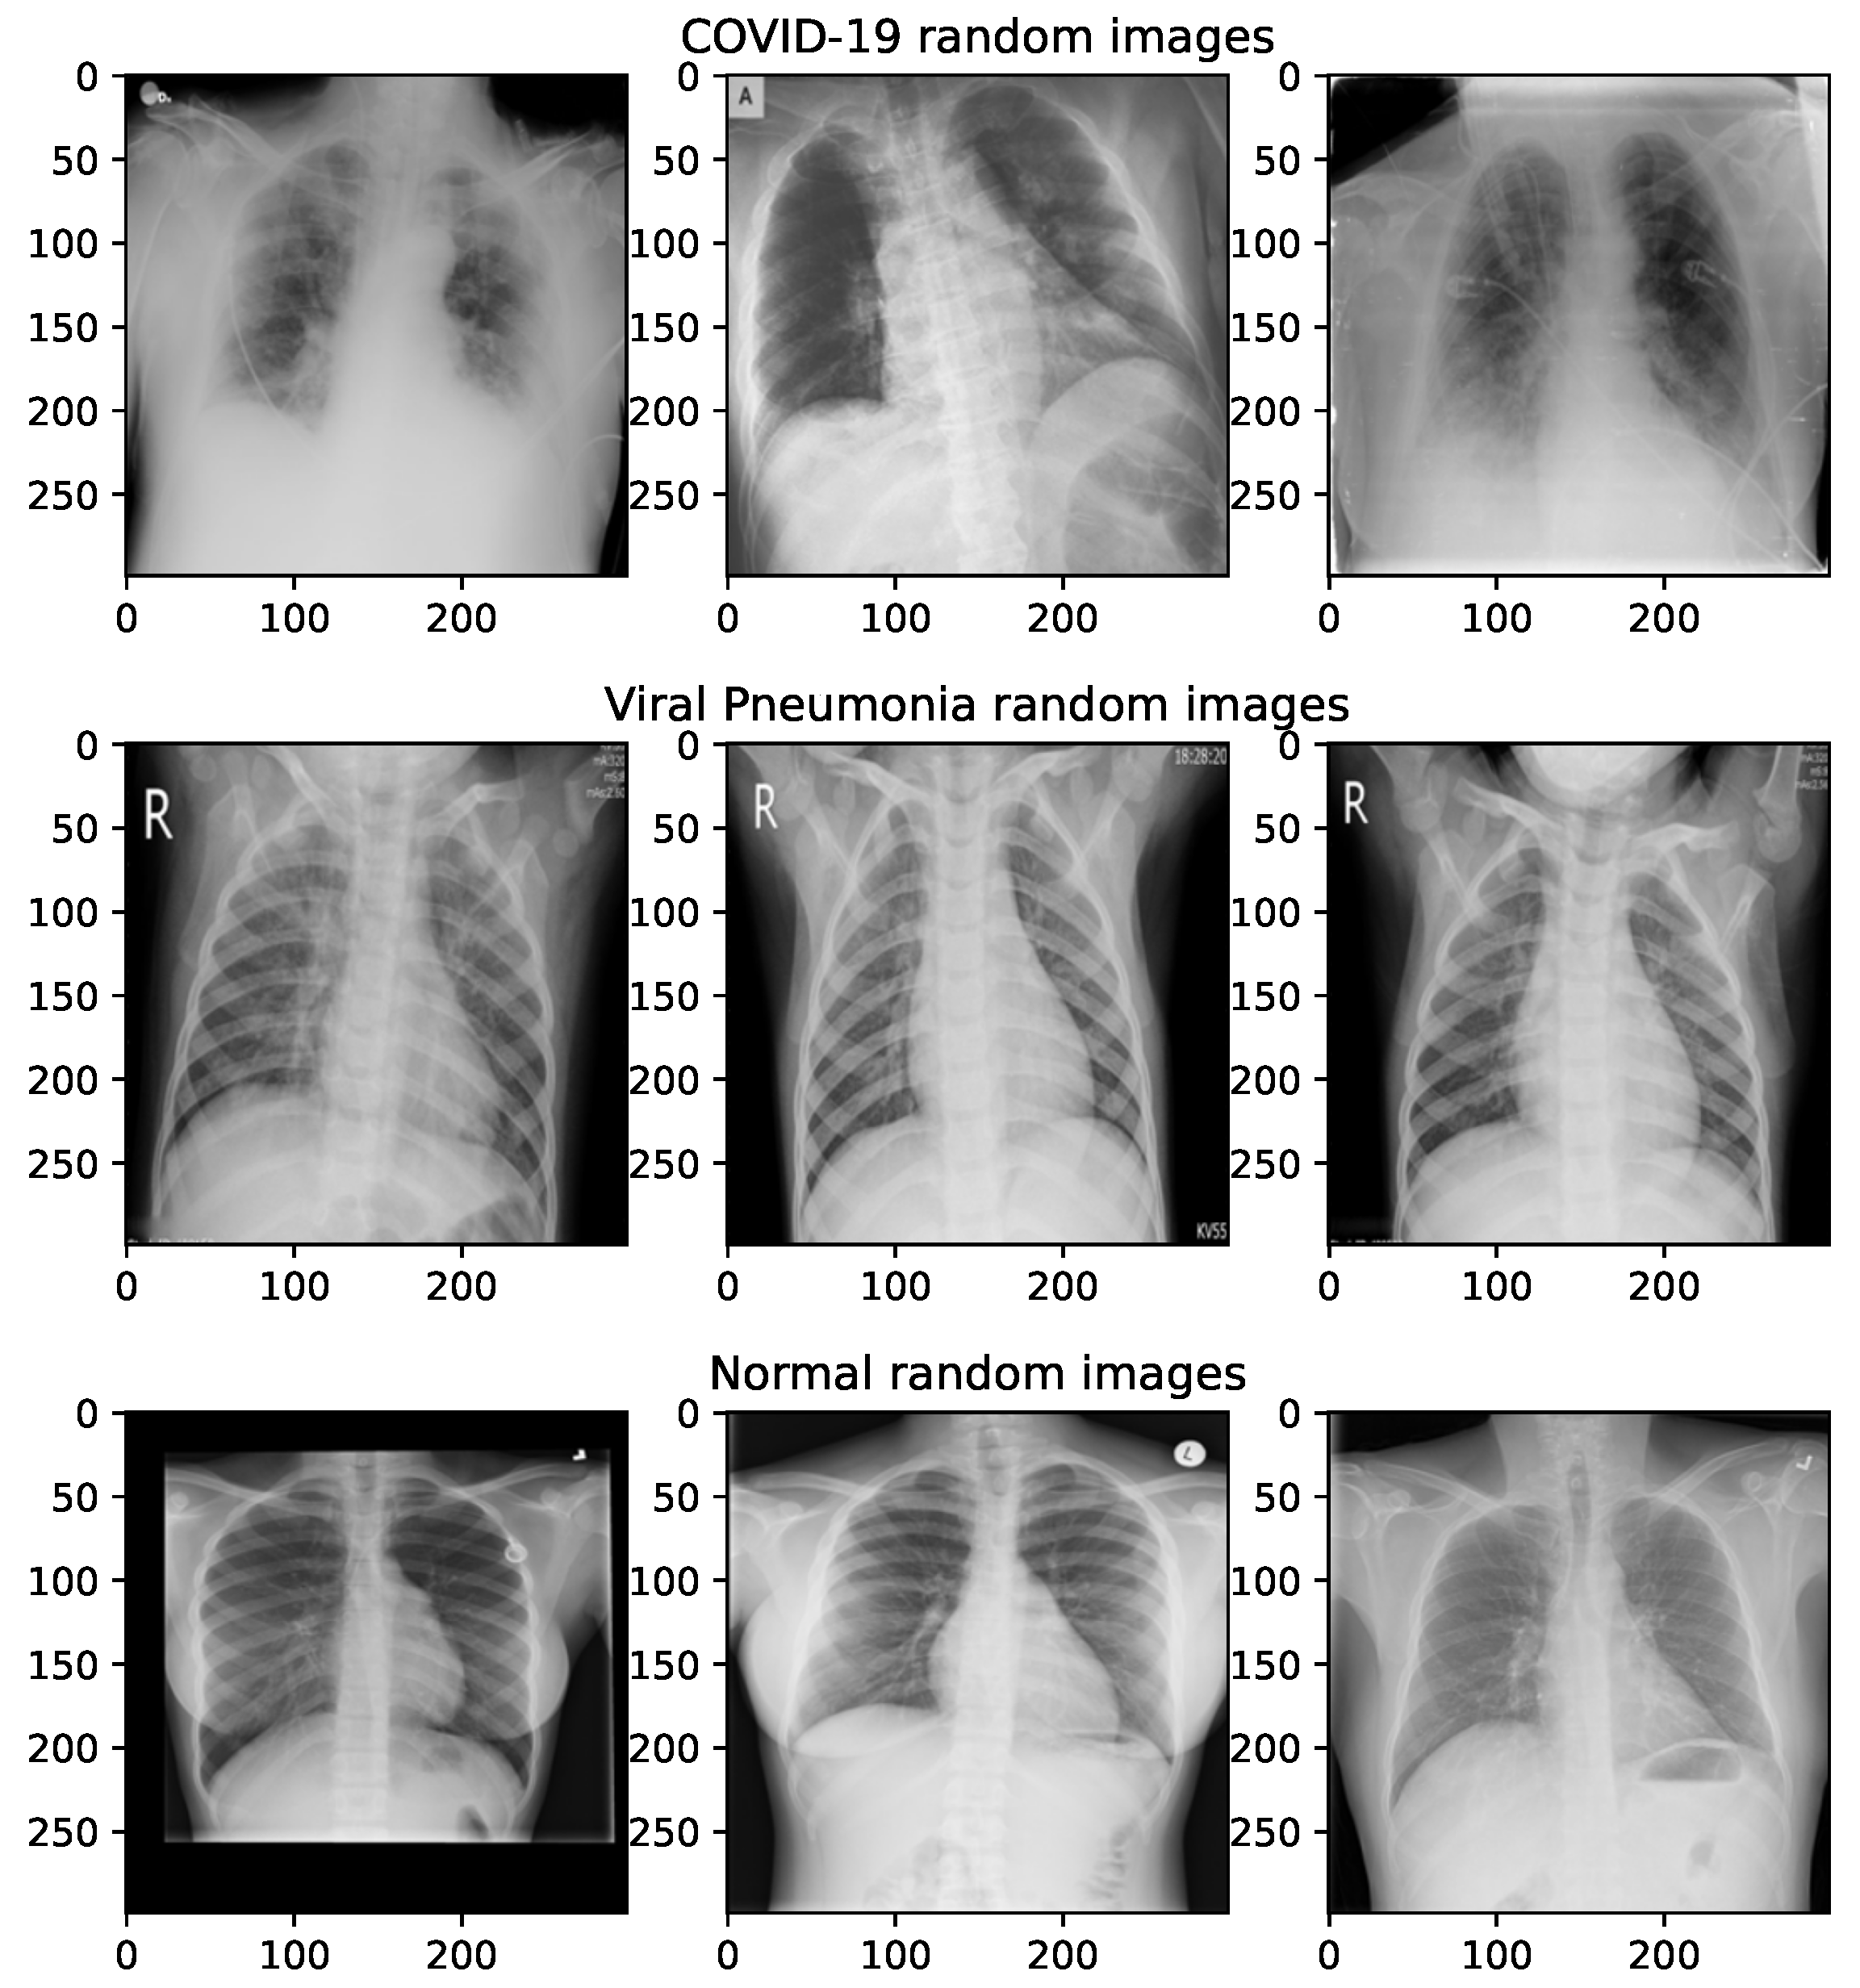

The majority of images for the dataset employed in this research is taken from the COVID-19 radiography database, which can be retreived from the following URL: https://www.kaggle.com/datasets/tawsifurrahman/covid19-radiography-database (accessed on 25 October 2022). The lung opacity images are excluded, and the remaining three groups are taken for experiments. The images are categorized as follows: normal (class 0), COVID-19 (class 1) and viral pneumonia (class 2). The retrieved dataset includes sets of 3616, 10,192 and 1345 images for COVID-19, normal and viral pneumonia classes, respectively. The COVID-19 radiography database images were also employed in other research [33,34]. Random sample images from the COVID-19 radiography database are shown in Figure 6.

According to the above description, the COVID-19 radiography repository is unbalanced, containing a majority of non-infected (normal) lung images. Since the area of the proposed research is not related to addressing imbalanced datasets, the utilized dataset is balanced so that each class has 4000 images. The balancing is performed in the following way: a random subset of 4000 normal images is taken from the original set, and the COVID-19 images are supplemented up to 4000 by taking some X-ray COVID-19 images from the Augmented COVID-19 X-ray Images Dataset [136] and by generated dedicated augmented images for this research, while 2655 viral pneumonia additional figures are generated by performing geometric augmentation of the original ones.